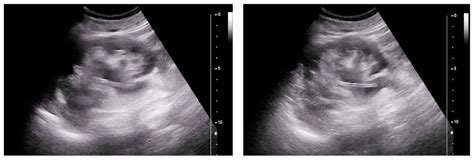

A urinary tract stent procedure involves the insertion of a thin, flexible, hollow tube—the stent—into the ureter. The primary purpose of this device is to hold the ureter open, ensuring that urine can travel freely from the kidney to the bladder. Without this pathway, a blockage can cause urine to back up into the kidney, leading to severe pain, potential infection, and possible long-term kidney damage.

Most patients return home shortly after the urinary tract stent procedure. While you can generally return to your daily activities within a day or two, it is crucial to listen to your body. You may experience symptoms such as flank pain during urination, minor blood in the urine (hematuria), or a constant need to empty your bladder. These symptoms are generally manageable with prescribed pain relief and increased fluid intake.